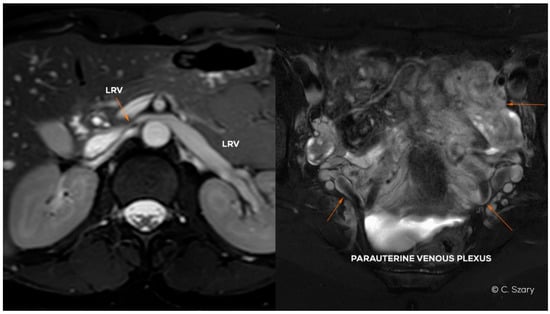

4.2. Grading of Ovarian Veins Insufficiency

| øLOV | incLOV | lPUV | bLIILV | øROV | incROV | rPUV | bRIILV | |

|---|---|---|---|---|---|---|---|---|

| GI | <6 | (−/+) | <5 | <5 | <5 | (−) | <5 | <5 |

| GI/II | 6–6.5 | (+) | <5.5 | <5.5 | <5 | (−) | <5 | <5 |

| GII | <7 | (+) | <6.5 | <6 | <5.5 | (−) | <5.5 | <5.5 |

| GII/III | 7.5–8 | (++) | <7 | <7 | <6 | (−/+) | <6.5 | <6 |

| GIII | >8 | (++) | 7–8 | <7.5 | <7.5 | (+/++) | <7 | <6.5 |

| GIV | >10 | (+++) | >8 | >8 | >8 | (+++) | >7.5 | >7 |